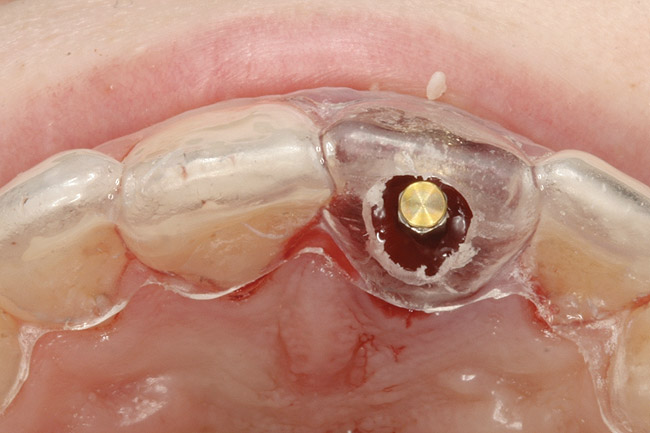

The osteotomy was started slightly palatally in alignment with the surgical guide, using a 2.1-mm precision drill (Figure 13) and finalized with shaping drills under copious external irrigation with sterile water. Special attention was paid to overcorrecting the osteotomy preparation toward the palate, where the bone is denser. An implant in this area—especially a tapered implant, as was used here—will usually veer toward the facial surface during insertion. Using the surgical guide to superimpose the central axis of the implant on the previous location of the central incisor’s cingulum facilitates accurate positioning (Figure 14).

The periodontist positioned a 4.3-mm x 16-mm regular-platform implant flush with the facial crest and 1 mm subcrestally interproximally (Figure 15), with a manually driven final seating torque value > 50 Ncm, followed by hand-tightened attachment of the immediate temporary abutment.

Figure 13  Initial osteotomy preparation with 2.1-mm precision drill, site No. 9. Priority level: 3.

Figure 13

Figure 14  Appropriate alignment of immediate temporary abutment, central axis of implant with cingulum area of surgical guide, incisal view.

Figure 14